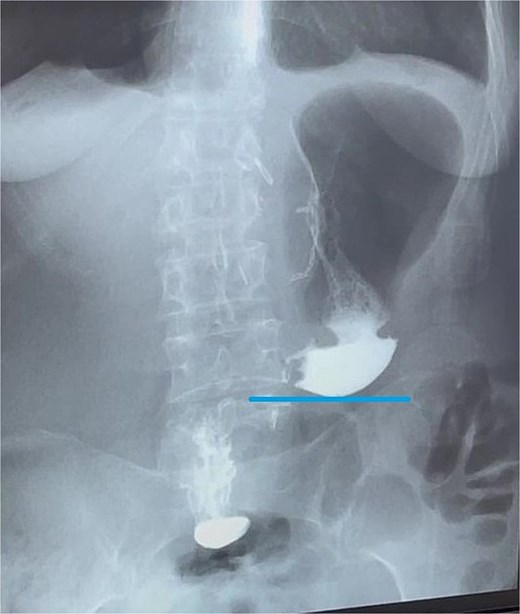

At this admission, the patient reported feeling “Bloated in the stomach, unable to eat solid foods, belching, bitter taste in the mouth, and weight loss (7 kg). BMI was 16.1 upon admission and showed signs of malnutrition” (Fig. 1). Gastric and duodenal radiography on 1 April 2025 showed the distal stomach located in the pelvic projection range, and the stomach had not emptied after observation for 2 hours (Fig. 2A). Combined X-ray and computed tomography (CT) findings revealed severe gastroptosis (Fig. 2B), and repeat endoscopy indicated pyloric obstruction, with difficulty passing the endoscope through the pyloric ring. Ulcer stenosis at the ESD site led to deformation of the gastric antrum and GOO, with chronic food retention and continuous gastric acid stimulation causing scar healing (Fig. 3). Given the extensive stenosis, EBD treatment was deemed likely ineffective. Prior to surgery, and to compensate for the nutritional deficiency, the patient received enteral nutrition with “Leovit ONCO” according to the clinic’s protocol, and laparoscopic-assisted distal gastrectomy with Billroth I anastomosis was planned.

Pre-operative imaging confirming GOO. (A) X-ray of the stomach and duodenum with contrast medium. Line indicates the lower border of the stomach. (B) CT scan of the abdomen with intravenous contrast. Line demarcates the lower border of the stomach.